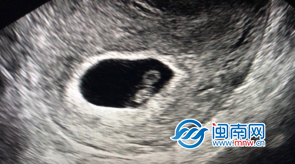

| 闽南网8月16日讯( 福建日报新媒体·闽南网记者 李昌乾 通讯员 黄才耀 谢珺 )近日,漳州市医院生殖医学科迎来了首例试管婴儿的成功妊娠,这个新生命的萌芽不仅是一个幸福家庭的新起点,也是该院生殖医学科的一个里程碑,标志着该院辅助生殖技术水平迈入新阶段。 漳州一对夫妇终圆好“孕”之梦 孩子是生命的希望和延续,也是大多数中国家庭的殷殷期盼。但是不孕不育症夫妇的漫漫求子之路却常常充满心酸和坎坷。其中,郑女士夫妇也是求子大军中一员。结婚多年未孕的郑女士夫妇于2018下半年开始在该院生殖医学科就诊,期间行四次宫腔内人工授精(IUI)均未受孕,多次失败也使得夫妇俩焦虑而沮丧。终于,随着该院生殖医学科顺利通过体外受精-胚胎移植(IVF-ET)试运行评审,郑女士夫妇成为了首批在该院接受该助孕技术治疗的患者,他们的求子之路也迎来新的曙光。 ![]() 据介绍,今年6月,郑女士夫妇顺利进入了IVF治疗周期,经历了一系列降调节、促排卵、体外受精、胚胎培养等过程,最终在7月14日,选择移植了两枚胚胎,术后给予精准保胎治疗,移植15天后检查HCG结果显示郑女士怀孕了,移植后28天B超检查一切正常,这一好消息令患者及所有医护人员均兴奋不已,祝福郑女士夫妇终圆好“孕”之梦。 填补漳州辅助生殖领域多项空白 据了解,随着不孕不育患者比例的上升,辅助生殖技术也越来越受到人们的关注。体外受精-胚胎移植技术,俗称“试管婴儿”技术,是将从妻子体内取出卵子和通过优选后的丈夫的精子,在实验室体外培养系统中受精,培养成胚胎时再移植到女性子宫内,通过母体孕育胎儿,这一技术已成为越来越多的不孕患者成功孕育下一代的希望。漳州市医院生殖医学科是漳州市首家并且是唯一一家开展辅助生殖技术的医院,已有多年不孕不育诊疗经验,并于2019年4月顺利通过了体外受精-胚胎移植试运行评审,正式获得了开展第一代试管婴儿(IVF)和第二代试管婴儿(ICSI)技术的资质,填补了漳州市在辅助生殖领域的多项空白。 另据介绍,试管婴儿技术是一项高精尖技术,对场地设备、实验室条件、人员配备等都有很高要求,漳州市医院生殖医学科在筹备过程中获得院领导全方位的支持,助力科室发展,目前,在李玲主任的带领下,科室人员对未来有充分的自信。李玲主任、吴雪斌主任具有丰富的不孕不育诊疗及妇科手术经验,曾帮助众多患者解决生育问题;科室医护人员均在知名生殖中心接受过专业培训,理论扎实技术过硬;科室配备最先进的仪器设备,保证稳定适宜的胚胎培养条件及手术环境;同时,与省内多家生殖机构协作,保证患者获得专业的治疗。首例试管婴儿移植的成功无疑是对这些的一次肯定。 ![]() 那么,什么情况适用试管婴儿技术呢? 其实,这一技术适用于多种病因的不孕症,如输卵管性不孕、部分子宫内膜异位症、多囊卵巢综合征、不明原因性不孕以及少、弱、畸精症等。其治疗过程主要包括术前常规检查,药物诱发排卵,B超及血激素监测卵泡发育,超声引导下经阴道取卵,精液采集与处理,体外受精,胚胎培养,胚胎移植,剩余胚胎冷冻保存以及移植后黄体支持,适时抽血化验hCG和B超检查胚胎生长、发育等。 曾经,漳州地区的不孕症夫妇只能到周边城市甚至更远的地方接受试管婴儿技术治疗,费时费力,如今,情况已经改变,漳州市医院生殖医学科将以科学、严谨、负责的态度,让广大不孕不育患者在家门口享受最专业的服务,为更多家庭创造新“生”。 文章来源:闽南网 |